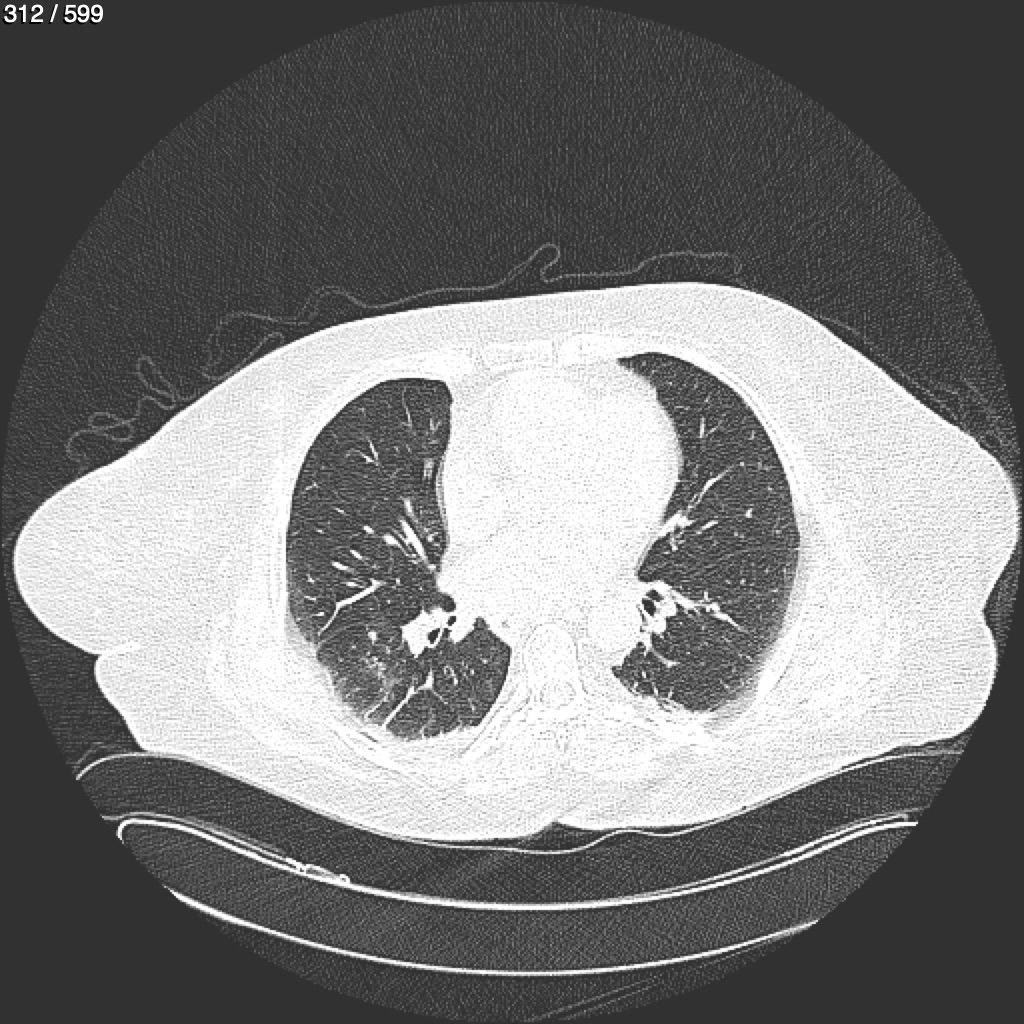

Home G​l​o​r​i​a​ ​G​l​a​d​y​s​ ​B​e​a​s​l​e​y​ ​-​ ​T​ó​r​a​x​ ​T​o​r​a​x​_​S​i​m​p​l​e​ ​(​A​d​u​l​t​o​)